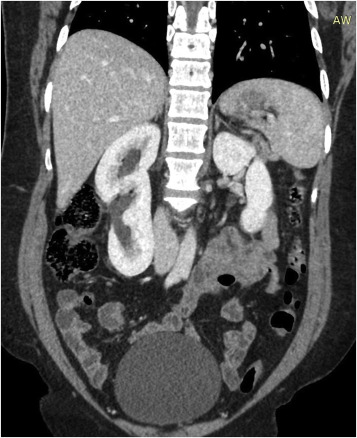

The supernumerary kidney is the rarest inherited kidney disorder related to the genitourinary system. The genitourinary system consists of the organs of the reproductive system and the urinary system. There are around 100 cases that are reported globally. Most of these cases include the abnormal growth of an additional kidney just beneath the right kidney, but it is smaller than the native kidney. However, the commonly reported symptom is unexplained lower right kidney pain. The supernumerary kidney can also be defined as the same kidney’s growth other than the two separate kidneys, which is defined as having two pelvic systems. These pelvic systems are formed by the renal pelvis containing a membrane or tissue layer, which functions as the funnel for the flow of urine and is connected with the single or double ureter.

The Supernumerary kidney is an additional kidney that abnormally grows by the side of the human body’s primary kidneys. It is observed through studies that it has its capsule and blood supply and is not fused with the other kidney. Most supernumerary kidneys are smaller in size, but they could be large as well. Treatment of supernumerary kidney disorder highly depends on the patient’s condition and the function of the kidney. If any patient is struggling with such symptoms, then he or she should take quick action.

We advise doing the nephrectomy, which means the surgery to remove a kidney or any part of the kidney. The treatment management of this condition is usually done as per the symptoms. If a patient experiences such symptoms, which could be diagnosed through ultrasound follow-ups and USG with excretory function assessment, the patient is advised to do early medication. However, if the symptoms worsen, and must remove the abnormally grown kidney immediately.